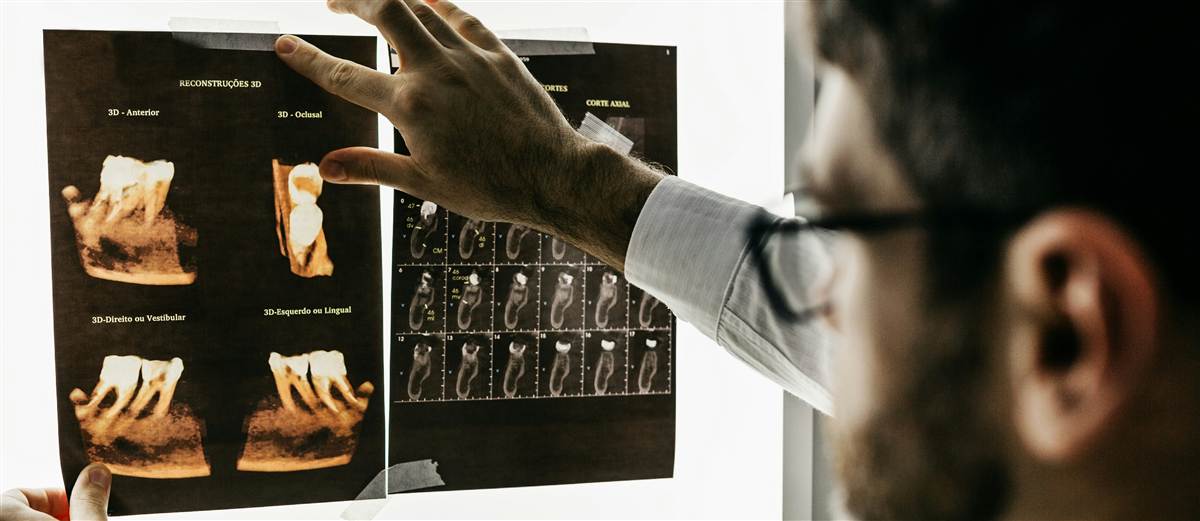

- Consultație și planificare (radiologic/CBCT)